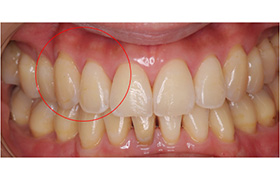

Before

After

歯牙移植(骨の移植)

むし歯や歯周病で歯を失った後に、通常必要のない親知らずを、なくなった箇所に移植することによって健康な歯並びを回復する事ができます。

※移植には適合のための条件があります。